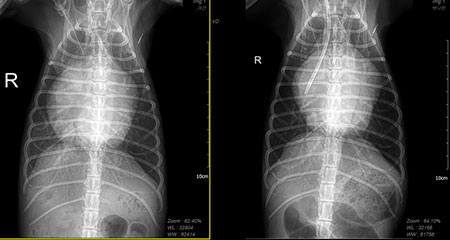

아마 이 아이에게는 모든 순간이 넘어야 하는 높은 산이었을 것이다. 멀리서 내가 할 수 있는 것은 응원 뿐. 그리고 다음날 환자의 방사선 사진이 메시지로 도착했다[그림 2, 3].

투석 만세다. 아이는 잠시 위기에서 탈출했다. 투석을 하면 신장도 위기에서 구해낼 수 있지만 폐수종도 초여과를 통해 해결할 수 있다. 이런 상황을 만들면 단 며칠 이뇨제 요구량도 감소한다.